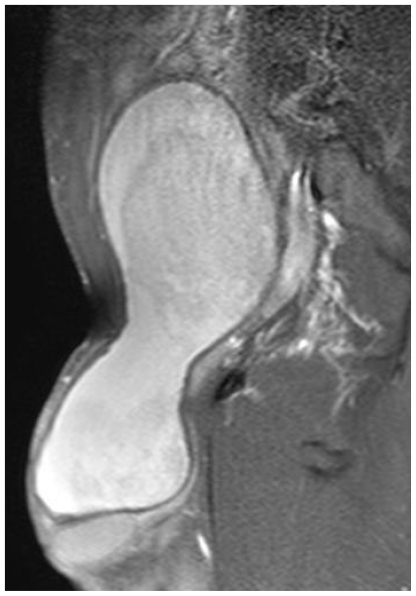

Figure 3.

24 Year old male with large hemorrhagic abdominolscrotal hydrocele: Gadolinium-enhanced T1-weighted axial image with fat suppression. Compared to the baseline, there is no Gadolinium enhancement apart from the right bursale-scrotal wall. On the ipsilateral side there is no enhancement of the bursal content. There is some Gad-enhancement at the level of the contralateral bursal wall (hyperintense for the blood). The absence of hyperaemia in the right scrotal bursa suggests a simple hydrocele. Also there is a shift towards right of the corpora cavernosa.